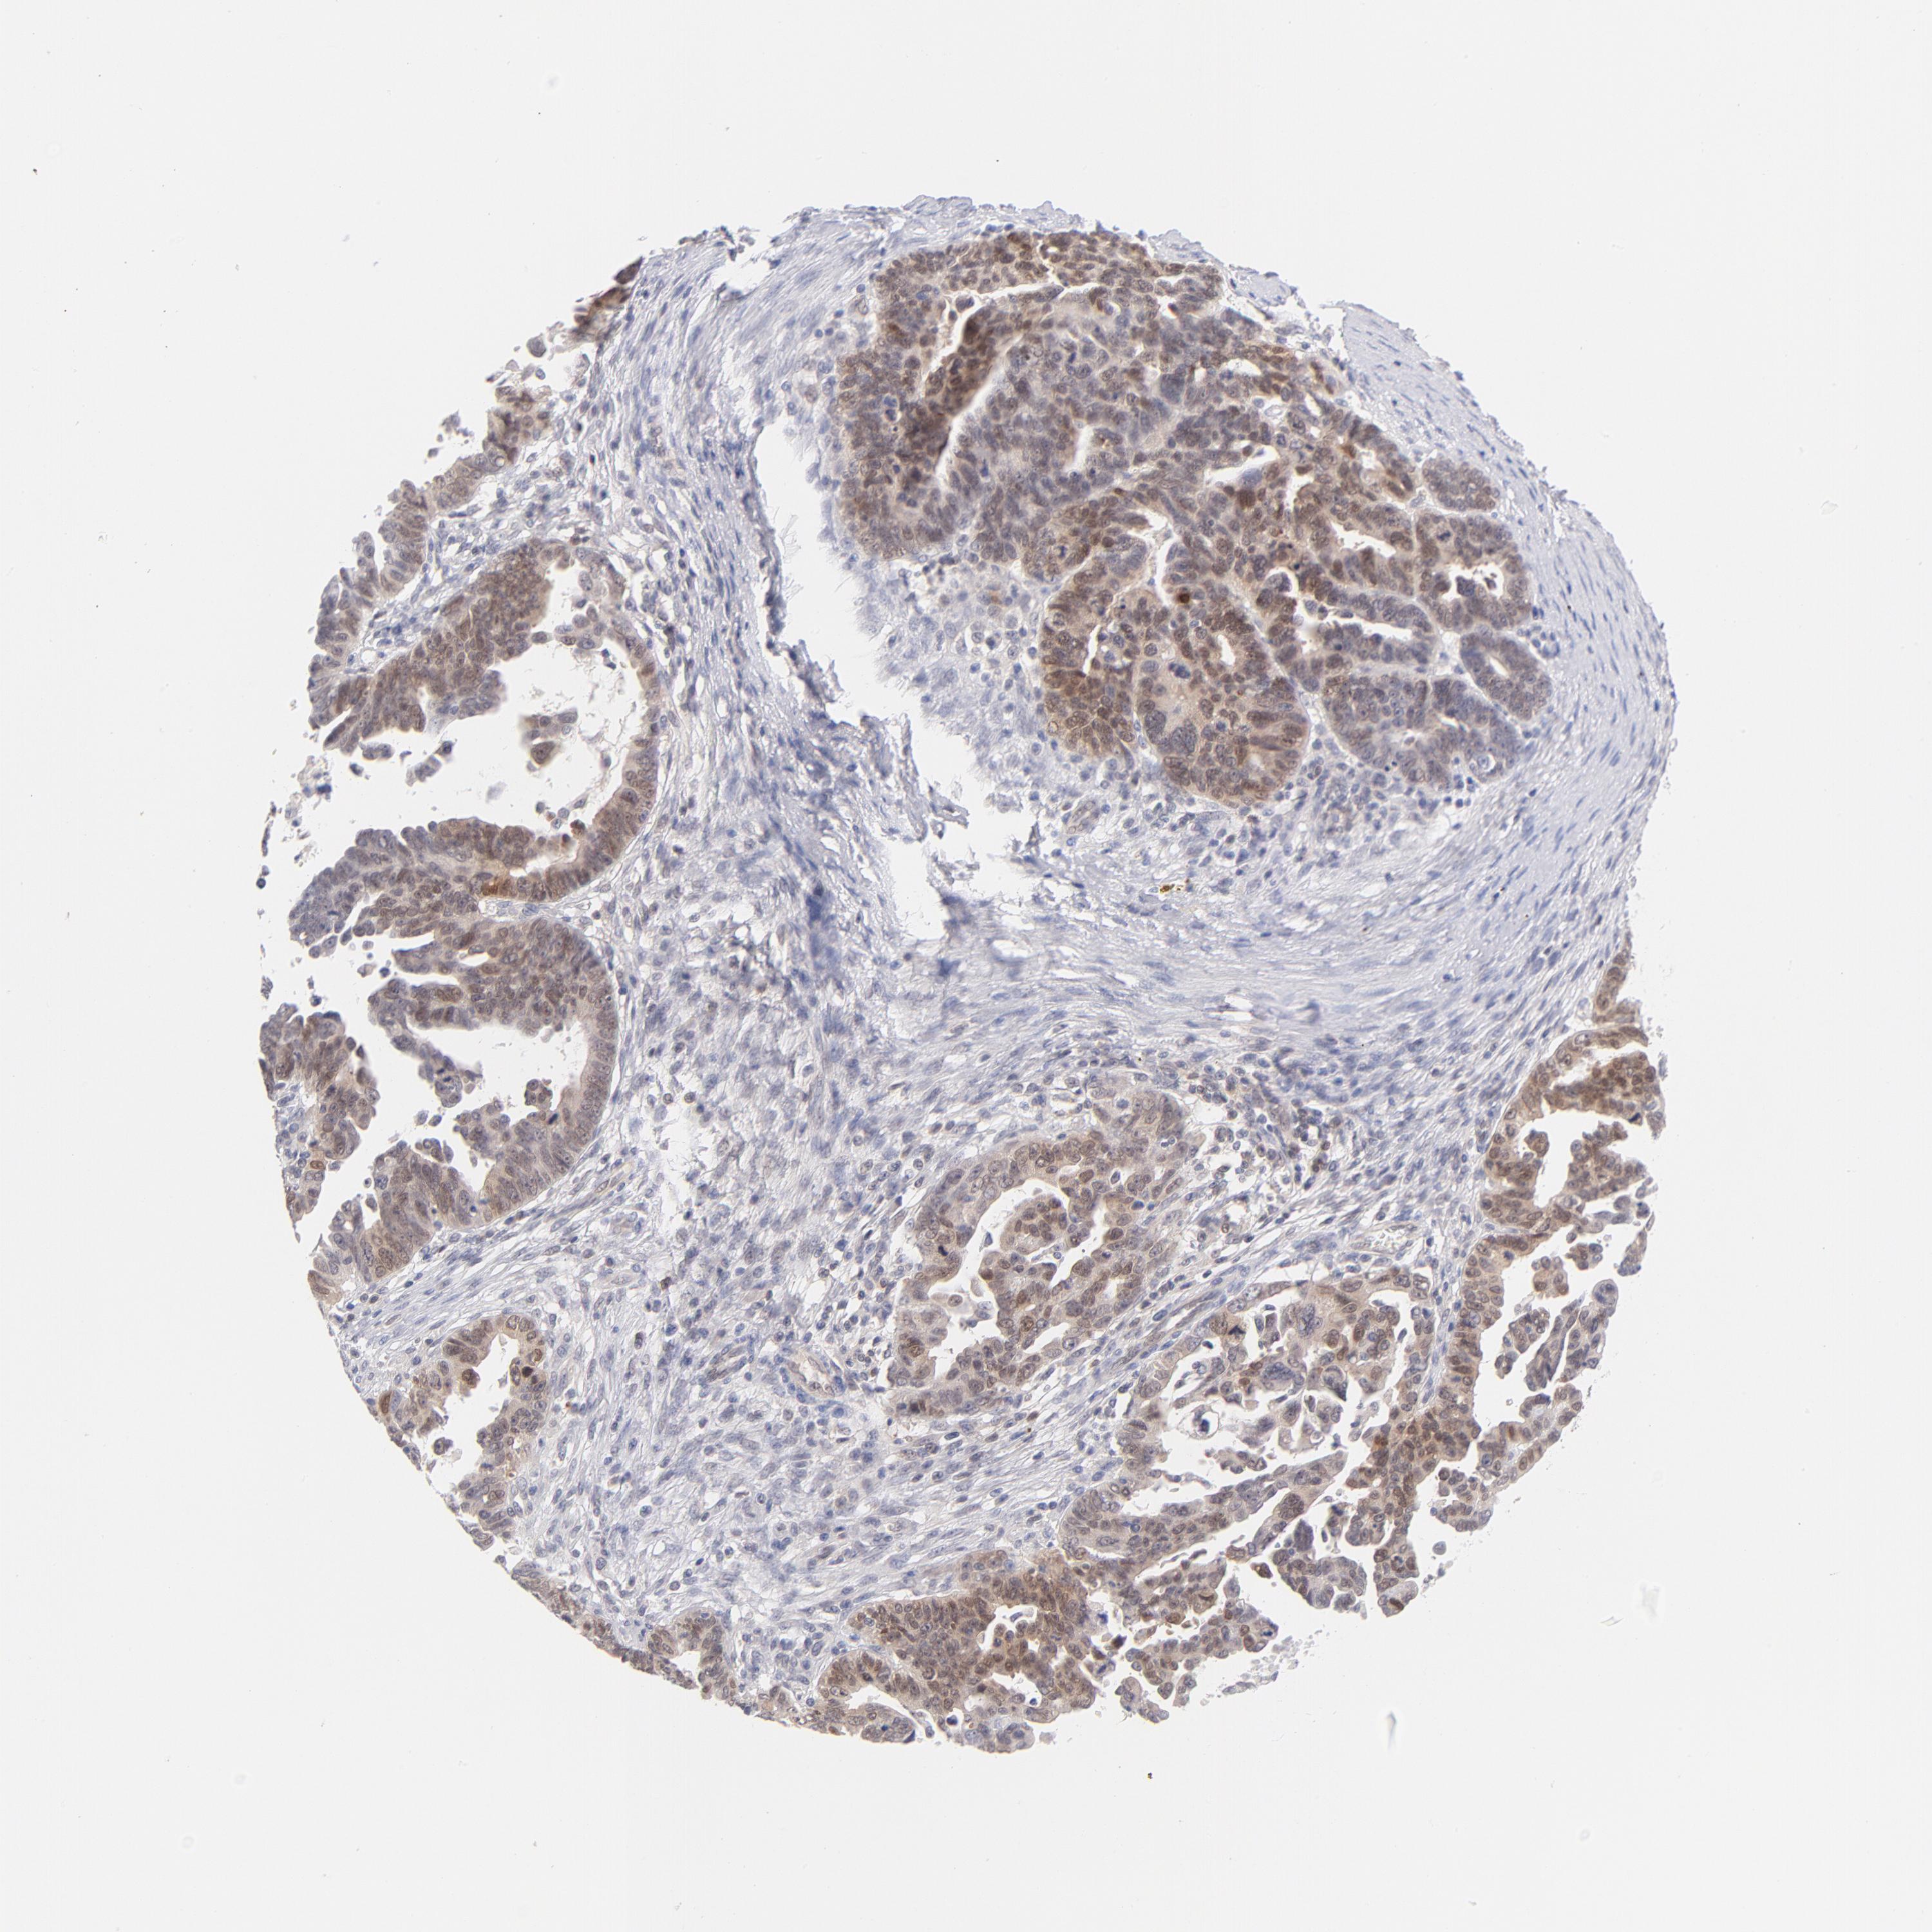

OVARIAN CANCER - Protein expressioni

A mouse-over function shows sample information and annotation data. Click on an image to view it in a full screen mode. Samples can be filtered based on level of antibody staining by selecting one or several of the following categories: high, medium, low and not detected. The assay and annotation is described here.

Note that samples used for immunohistochemistry by the Human Protein Atlas do not correspond to samples in the TCGA dataset.

Antibody stainingi

Antibody staining in the annotated cell types in the current human tissue is reported as not detected, low, medium, or high, based on conventional immunohistochemistry profiling in selected tissues. This score is based on the combination of the staining intensity and fraction of stained cells.

Each image is clickable and will lead to virtual microscopy that enables deeper exploration of all samples and also displays staining intensity scores, fraction scores and subcellular localization as well as patient and tissue information for each sample.

Antibody HPA011337

Antibody HPA024303

Antibody CAB003775

Staining

High

Medium

Low

Not detected

Cystadenocarcinoma, serous, NOS